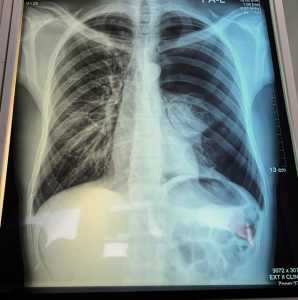

Here, we trained a group of mostly EM residents in core and advanced point-of-care ultrasonography, with several days dedicated to core exams- largely a review for these trainees that mostly had some, although very limited, exposure to ultrasound. The latter days were spent building and expanding on the knowledge from prior days with advanced ultrasound topics.

This high intensity training course had a strong focus on skill acquisition. To this end, each day was structured so that this a majority of the time was spent in skills lab, first with standardized patients, then the group would mobilize to the wards so that the learners could real time direct supervision. Patients with known or suspected pathologies, and those with undifferentiated presentations were scanned by learners, which aided in accelerated competence and confidence of the learner to perform the reviewed modalities.